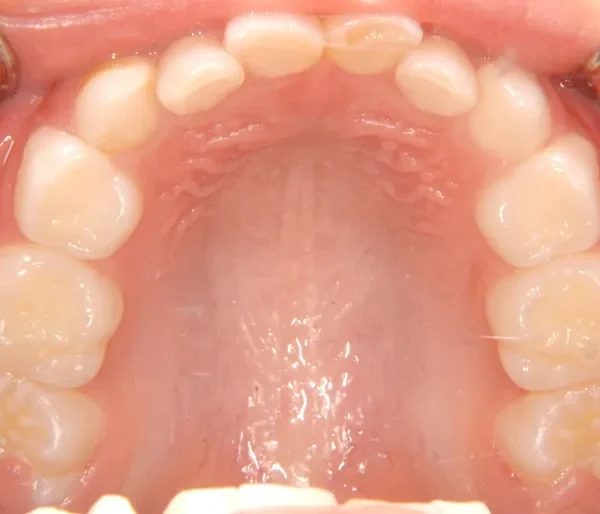

• 初診

初診時年齢 6歳まで (女性) 主訴 ガタガタ

診断名 叢生 装置名

状態 永久歯が生える隙間がない(叢生)

ガタガタ・でこぼこに生えている(叢生)

下の歯がずれて生えています。

こどもの歯は下の2本しか抜けていませんが、放っておくとガタガタがきつくなるので、早い段階からの治療としました。